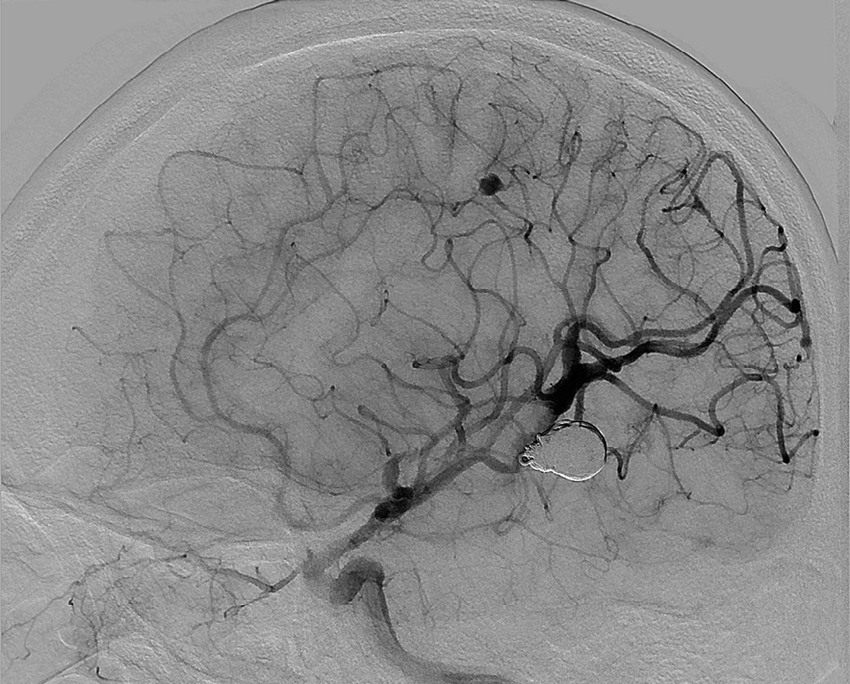

目前的显微手术技术已达到相当高的程度,既然颅内动脉瘤的较大危害是-一次出血造成的,并非由于外科手术,所以今后的注意力似应着重发现未出血的动脉瘤,及时给予处理。影像学的进一步发展,将能帮助解决这个问题。目前的MRA不需要造影剂,即能显示出全部脑血管影像。有些病种如多囊肾、主动脉缩窄和结缔组织病等容易伴发颅内动脉瘤,及时检查将会有所发现。